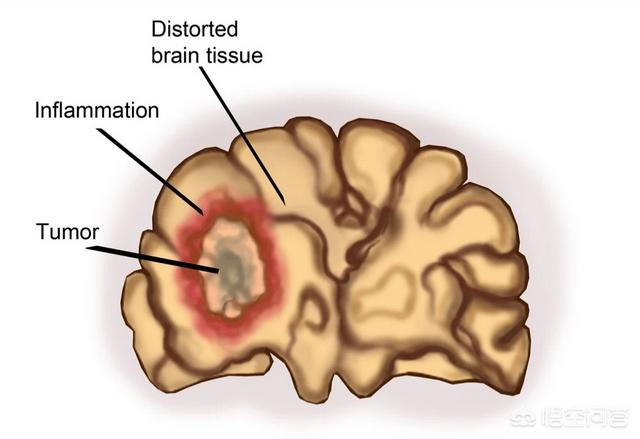

腫瘍は良性腫瘍と悪性腫瘍に分類され、良性腫瘍のほとんどは悪性化しないが、中には悪性化するものもある。しかし、医師は自分の経験に基づいて、治療が必要なものとそうでないものを判断します。

しかし、診察の結果、肝臓に病変が見つかり、その病変は非常に小さいものである必要があるが、経験上、これはゆっくりと成長し、最終的には転移する可能性のある悪性のものである可能性がある。その場合、医師は治療を勧めるだろう。後で体に取り返しのつかないダメージを与えることを考慮するからである。

逆に、良性腫瘍の中には悪性の可能性があり、将来のある時点で癌化する可能性があるものや、腫瘍が比較的大きく、臓器機能に支障をきたすため外科的切除が必要なものもある。

良性腫瘍は、生体の特定の組織で細胞が異常に増殖したもので、通常は被包性で膨張性に増殖するが、増殖は緩徐である。周囲の組織に浸潤することも転移することもないため、一般に健康に影響を及ぼすことはなく、中には一生変わらないものもある。後期になると、腫瘍が大きくなりすぎて周囲の臓器を圧迫し、患者さんが不快感を感じるようになるものもありますが、ほとんどが局所的な症状を示すもので、手術で切除すれば症状は緩和されます。